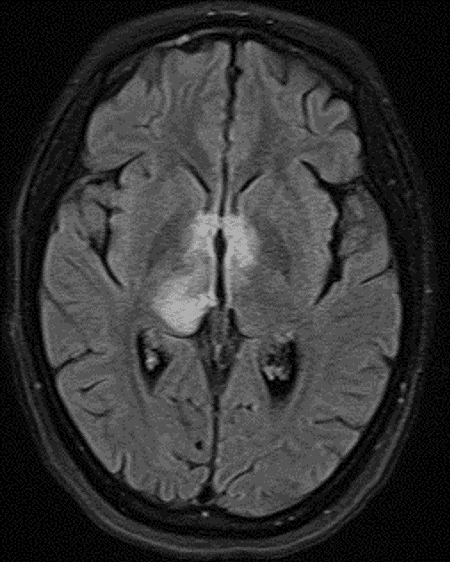

• T2/FLAIR signal hyperintensity in the right greater than left thalami and right greater than left dorsal midbrain with involvement of the periaqueductal gray matter, hypothalamus, anterior commissure, and mamillary bodies

• Areas of cystic change in the right thalamus and right eccentric midbrain

• No corresponding enhancement or restricted diffusion

FLAIR signal hyperintensity along the ependymal margins of the third ventricle and cerebral aqueduct, extending into the right greater than left thalami.